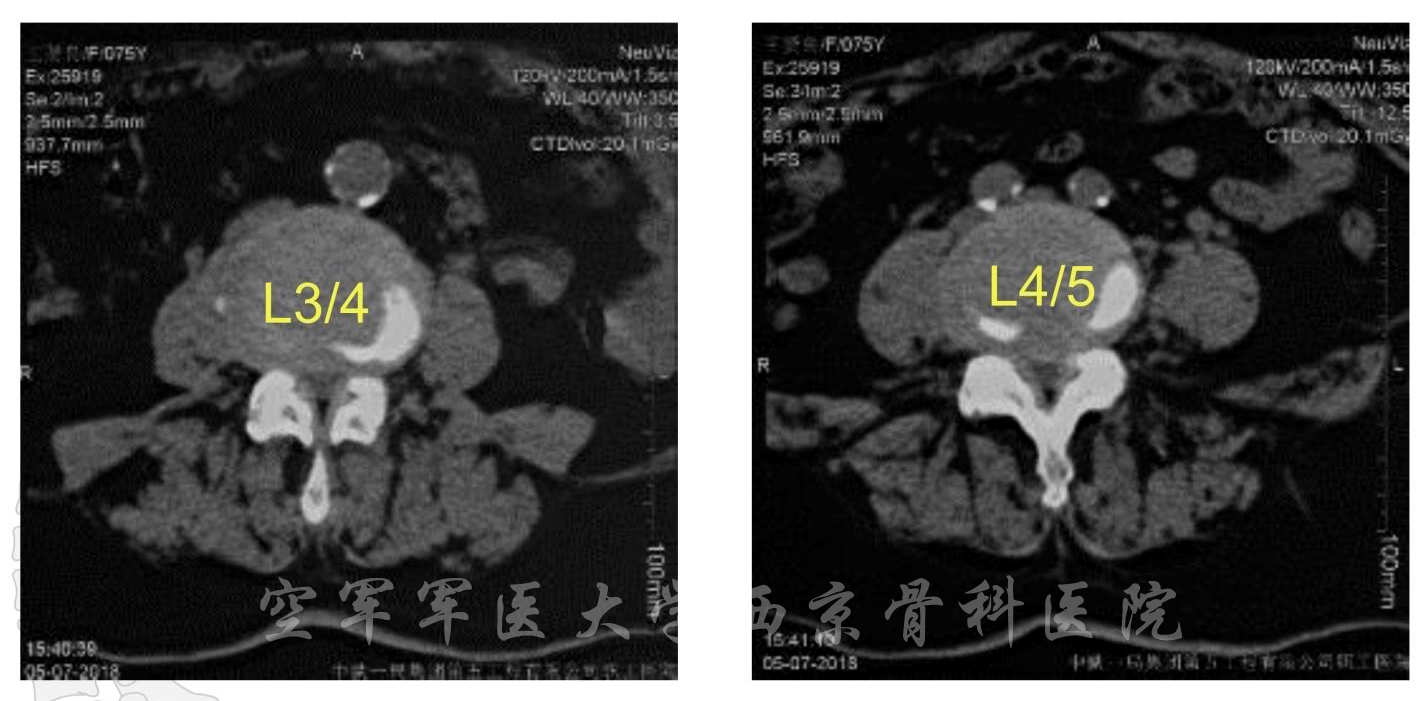

术前MRI

术前CT